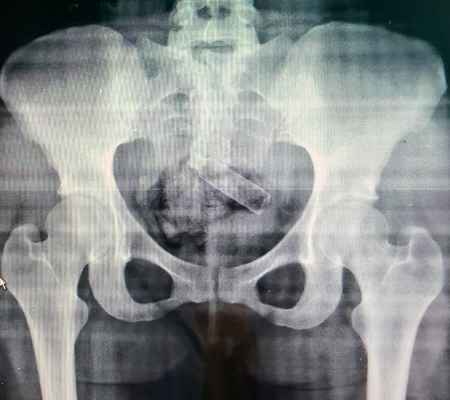

Ela foi conduzida para o Hospital de Urgência de Teresina (HUT) para a realização do exame raio-X, que identificou a droga escondida em sua região íntima.

A jovem passou por um procedimento, onde foram retirados três pacotes de maconha pesando 50 gramas e um recipiente de perfume da sua genitália.